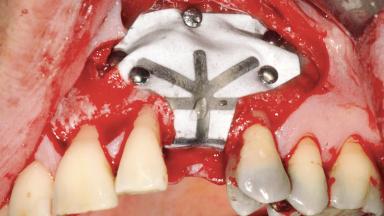

| Bone Augmentation | Staged|Vertical |

| Augmentation Materials | Autogenous chips|Membrane |